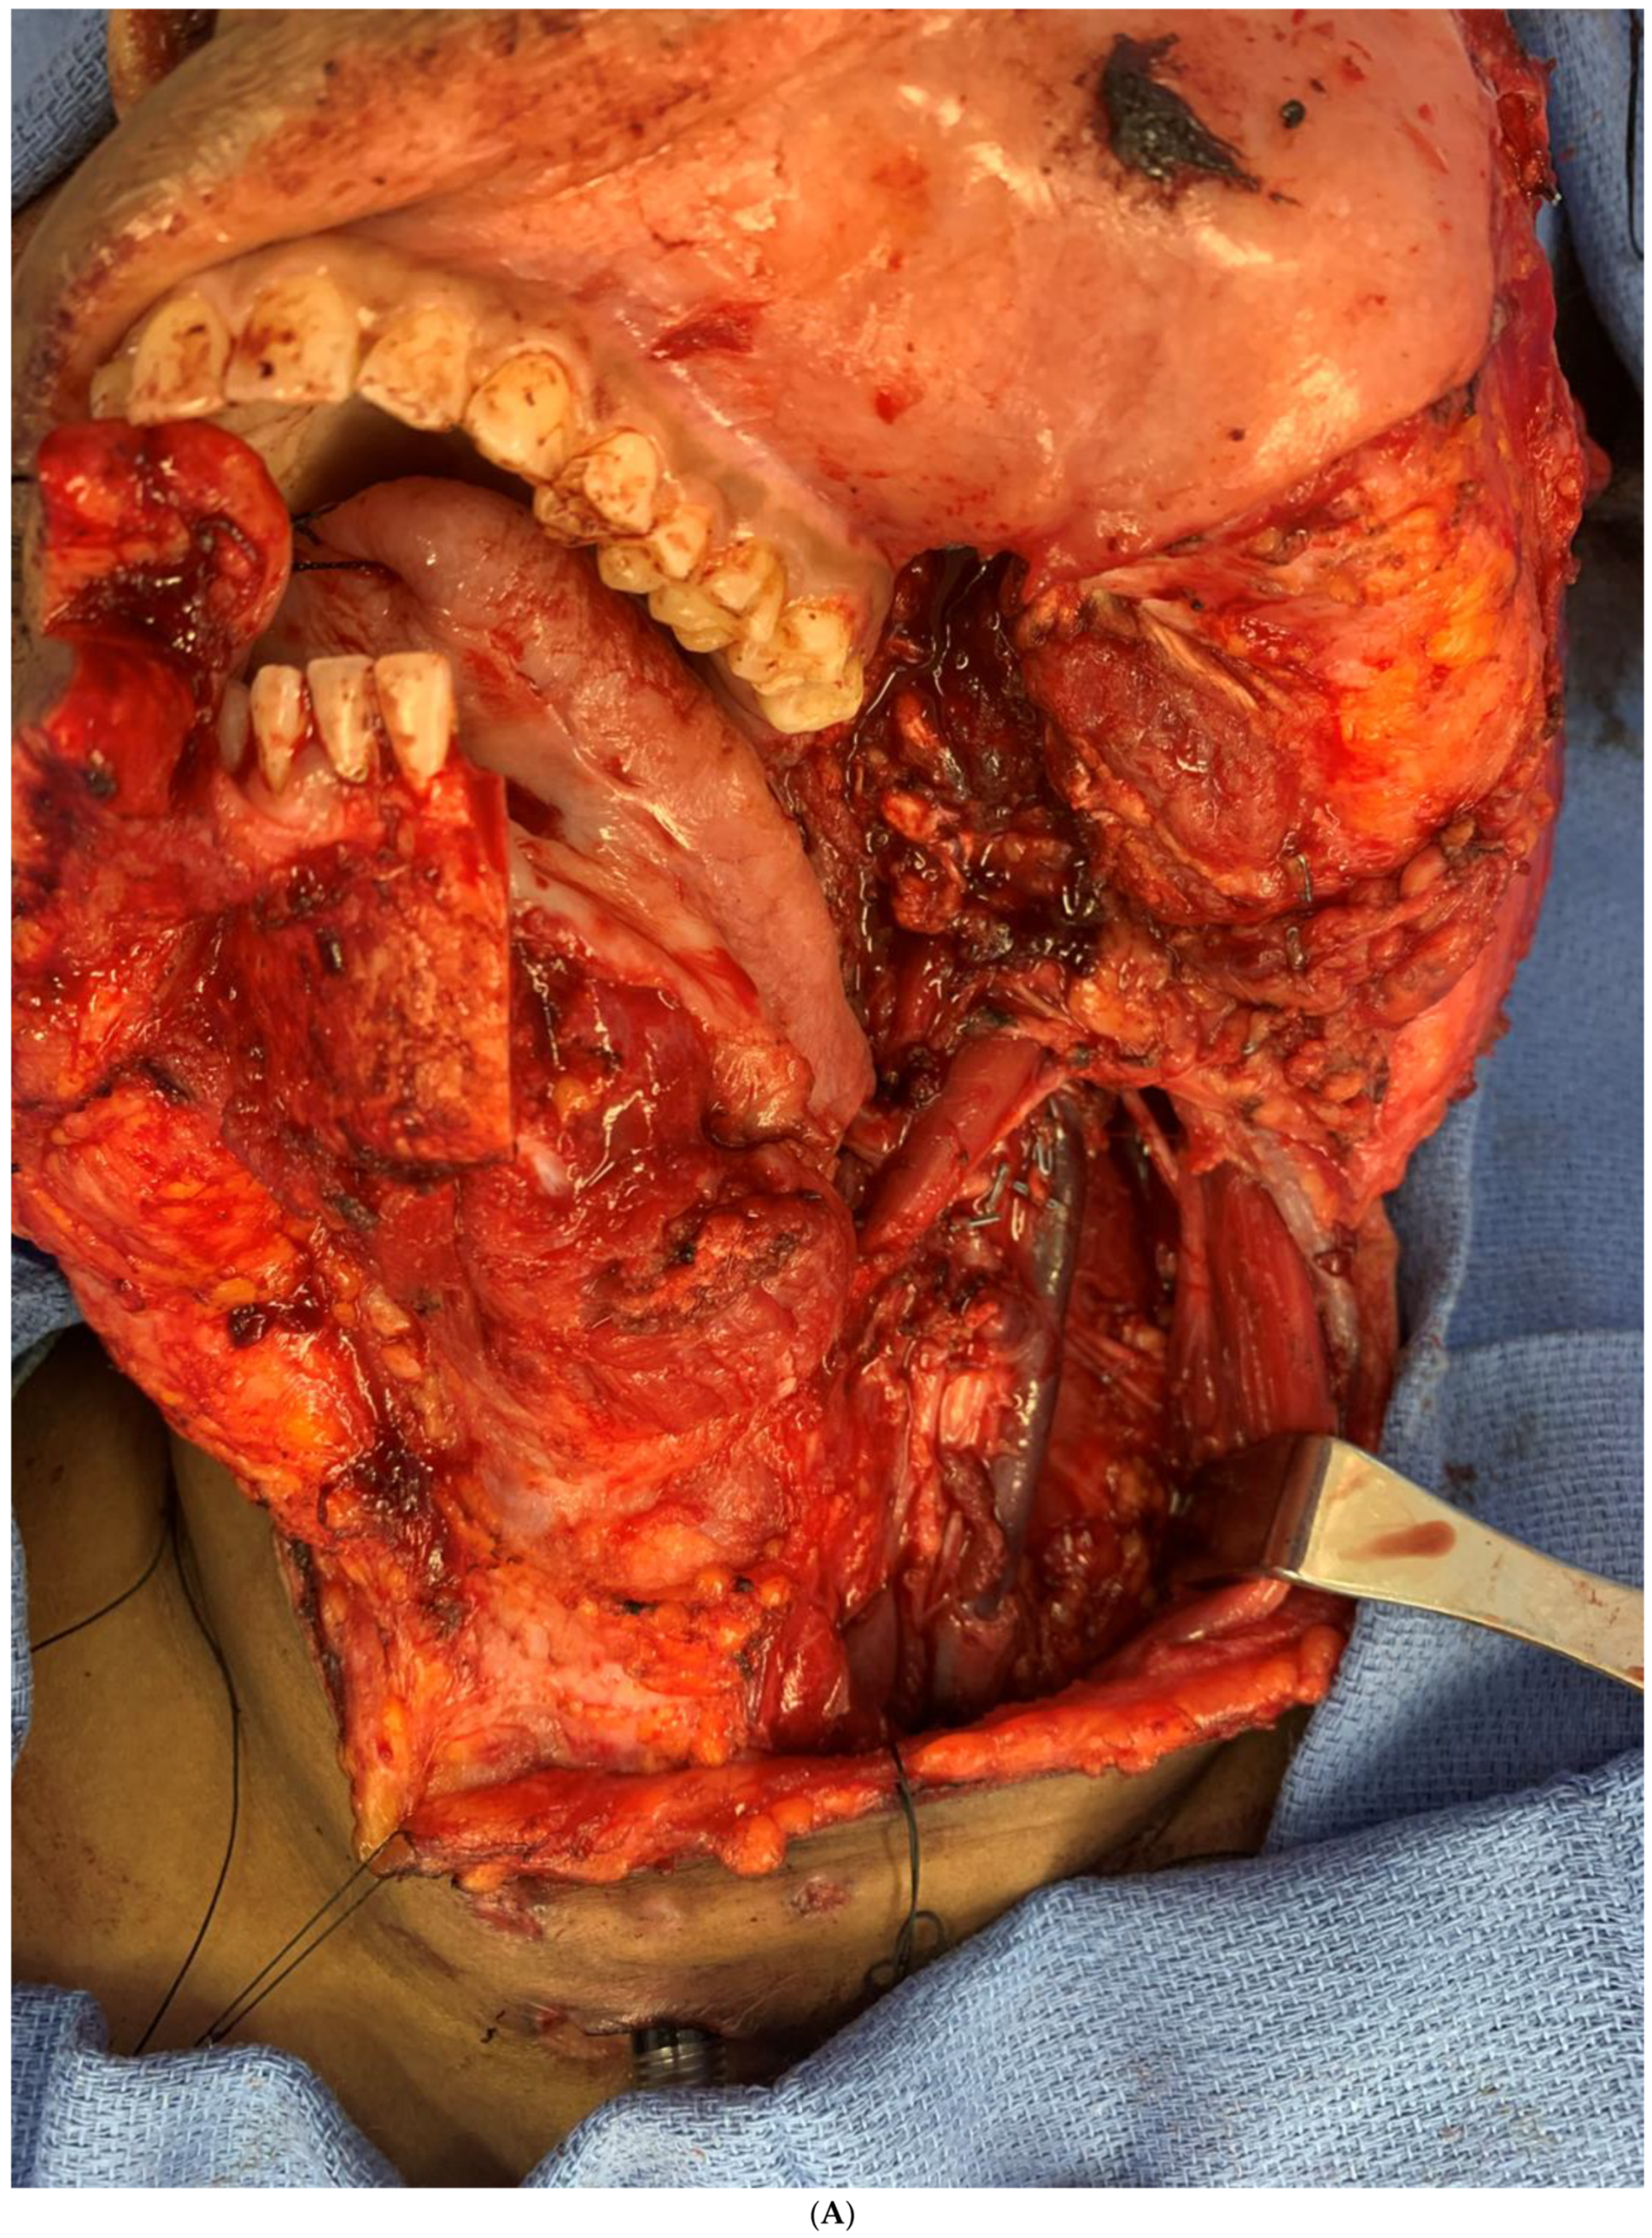

During recovery from chemotherapy, surgical planning (VSP) was used to plan the surgery. Based on the computer simulation, the planned surgery was to achieve 3 cm margins of bone and soft tissue around the tumor. Also, VSP was used to design the reconstruction using an osteocutanous free fibula flap with dental implant placement (Figure 6A,B). After about five weeks, the patient underwent a hemi mandibulectomy with disarticulation, lateral pharyngectomy, selective neck dissection (level I-III), and immediate reconstruction using an osteocutaneous fibula flap (Figure 7A,B and Figure 8).

Figure 7.

(A) Intraoperative images showing the surgical defect after the hemimandibulectomy and neck dissection. (B) The illustration shows the defect’s extent after the hemimandibulectomy, lateral pharyngectomy, and neck dissection.